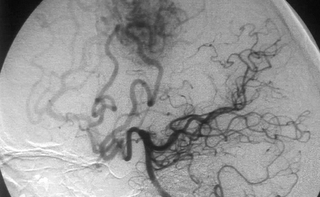

SPETZLER动静脉畸形(AVM)分级

分级指标 体积: 小 (<3cm ) 1 中 (3 - 6cm) 2 大 (>6cm) 3

邻近脑组织是否重要功能区: 否 0 是 1 静脉回流类型: 仅有脑表面静脉 0 有深部静脉 1

* 评分 = 上述分数之和,范围 1-5;另外有独立的第6级,指无法手术的病变 (切除不可避免地造成残疾性损害或死亡)

* 体积指在未放大的血管造影片上病变的最大直径。(和影响AVM切除难度的因素相关。如:供血动脉,盗血程度,等)

* 重要功能区指感觉运动、语言和视觉皮层,下丘脑和丘脑,内囊,脑干,小脑脚,小脑深部神经核。